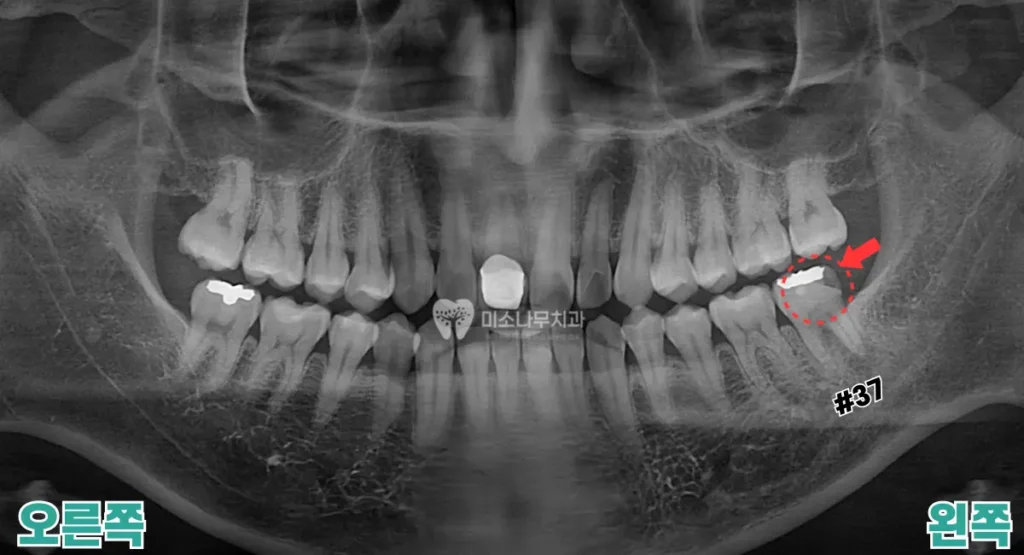

치료 전후 사례